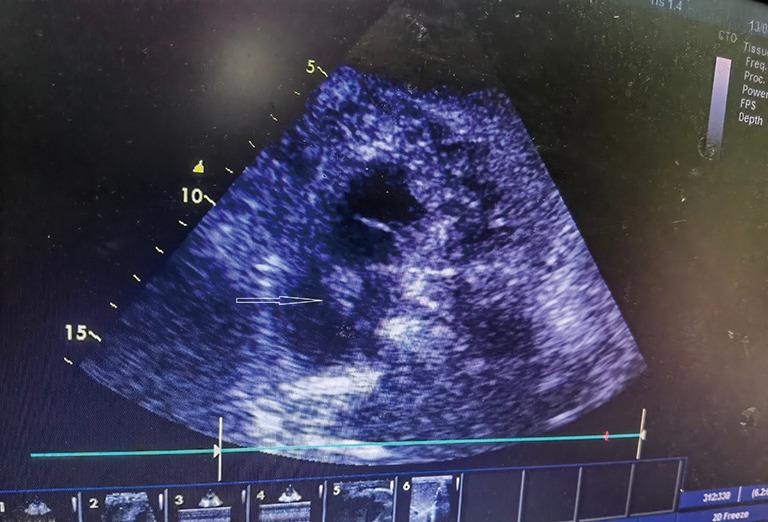

Herein, we report the case of a patient who presented with hypotension and tachycardia accompanied by an asymptomatic right leg deep vein thrombosis, right atrial thrombus, and pulmonary embolus. He had a history of radical resection of colon cancer 1 month prior. And he had developed chest tightness accompanied by stabbing pain in the chest area 1 day ago. He experienced an episode of syncope 8.5 hours ago. So he was referred to the local hospital. After the pulmonary computed tomography angiography (CTA) scan, he was diagnosed with pulmonary embolus and administrated with 5,000 u low molecular weight heparin. Then he was transferred to our hospital. On arrival in the emergency department, the bedside transthoracic echocardiography (TTE) revealed there was an enlarged right atrium and right ventricle, with a floating right atrial mass prolapsing through the tricuspid valve during diastole. The patient accepted anticoagulation treatment, but refused to undergo thrombolysis or surgical embolectomy. Eventually, the right heart thrombi (RiHT) floated to the left main branch of pulmonary artery. It was successfully treated by using AngioJet device and venoarterial extracorporeal membrane oxygenation (VA-ECMO). Our case provides clinical evidence supporting the feasibility and efficacy of AngioJet device and VA-ECMO in the treatment of the RiHT and PE.

在此,我们报告一例患者,其表现为低血压和心动过速,伴有无症状的右下肢深静脉血栓形成、右心房血栓和肺栓塞。他1个月前有结肠癌根治切除术史。1天前出现胸闷并伴有胸部刺痛。8.5小时前发生一次晕厥。因此他被转诊至当地医院。经肺部计算机断层扫描血管造影(CTA)检查后,他被诊断为肺栓塞,并给予5000单位低分子肝素治疗。随后他被转至我院。到达急诊科时,床旁经胸超声心动图(TTE)显示右心房和右心室增大,舒张期有一个漂浮的右心房团块经三尖瓣脱垂。患者接受了抗凝治疗,但拒绝接受溶栓或手术取栓。最终,右心血栓(RiHT)漂浮至肺动脉左主支。使用AngioJet装置和静脉 - 动脉体外膜肺氧合(VA - ECMO)成功对其进行了治疗。我们的病例提供了临床证据,支持AngioJet装置和VA - ECMO治疗RiHT和PE的可行性和有效性。